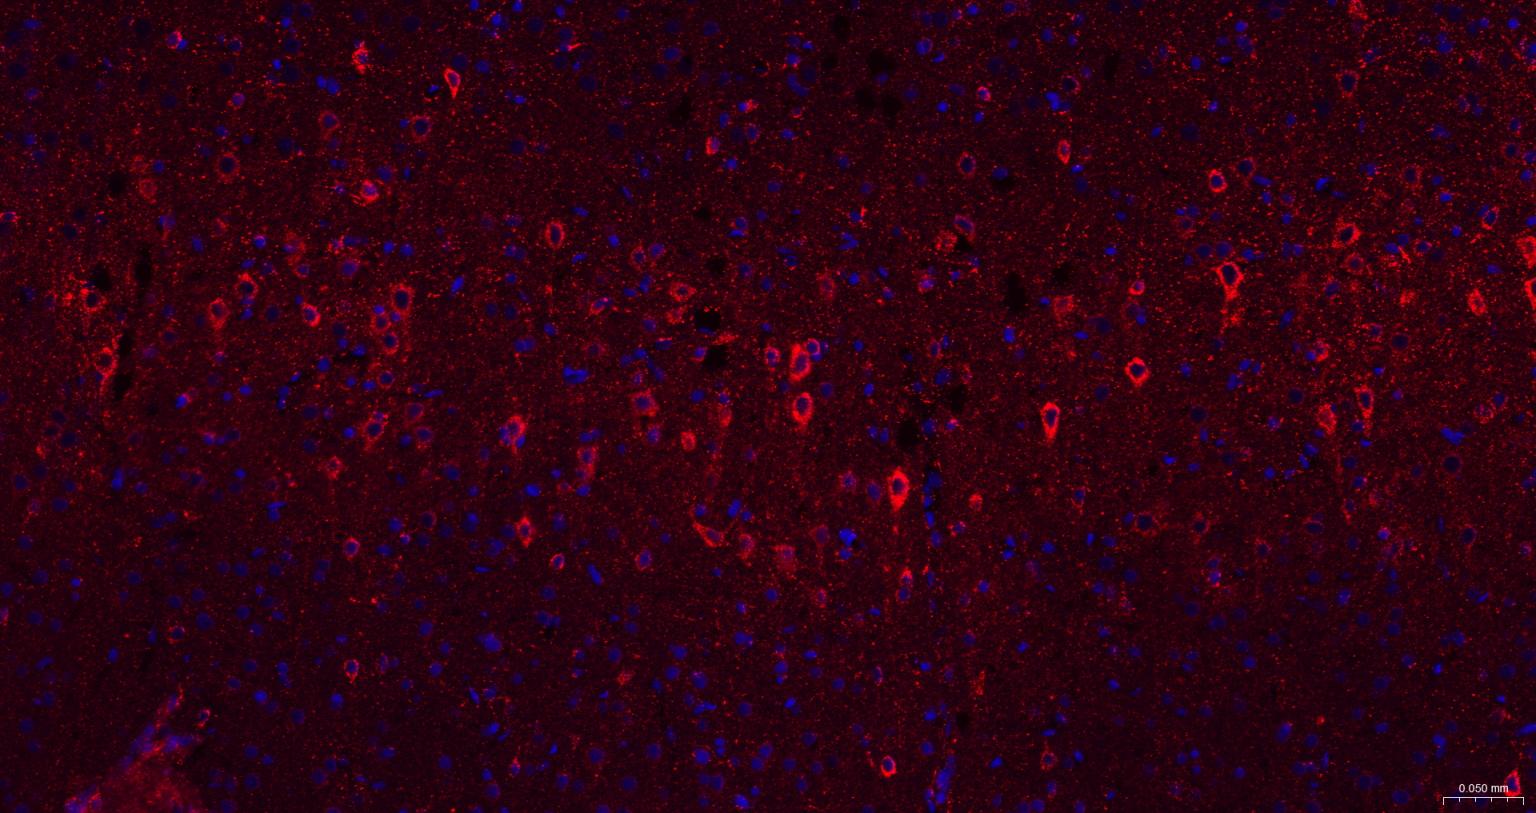

| IF | Human, Mouse, Rat | 1:100-500 | |